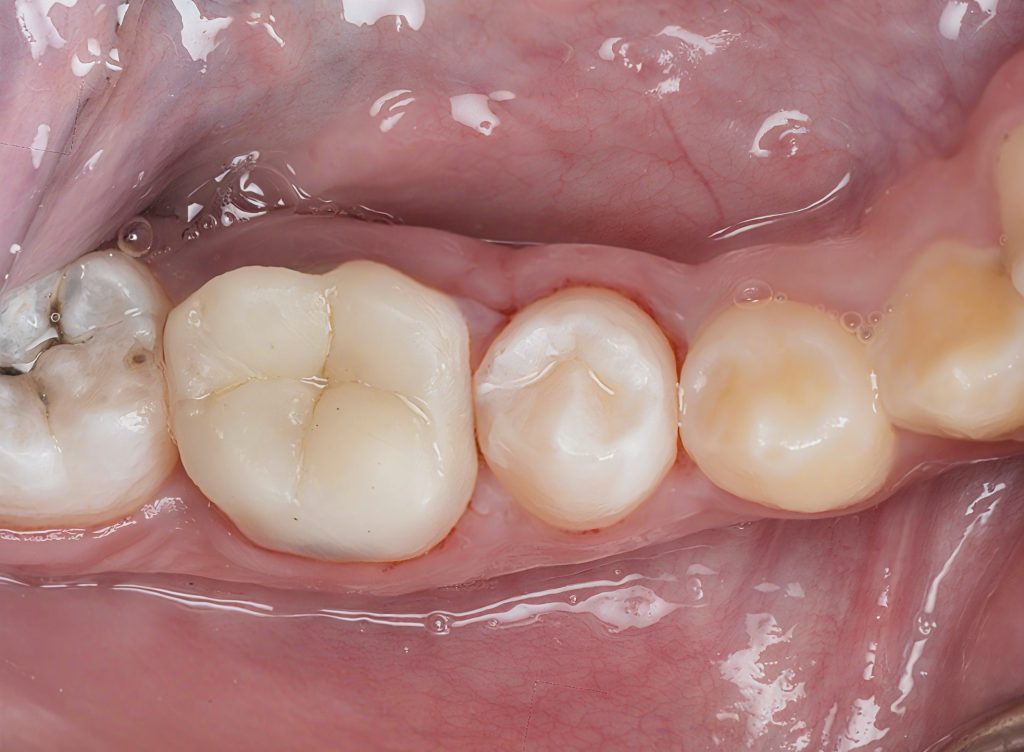

9. Final Outcome

(Images 20–21)

- Functional occlusal table restored

- Natural surface texture and anatomy

- Strong, bonded cuspal coverage

- Ideal contacts and sealed margins

- Radiographic confirmation of successful endodontic therapy

This is modern, conservative Zerodont dentistry — preserving structure, restoring biology, and maximizing long-term function.